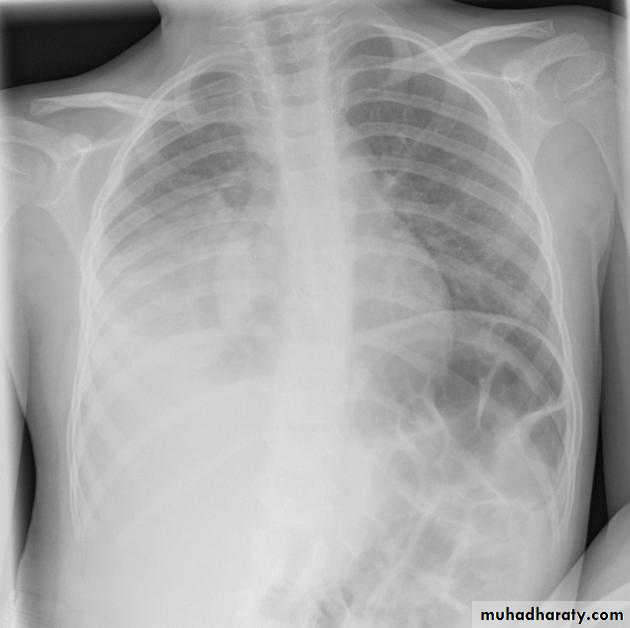

Left upper lobe collapse has distinctive features but can be challenging to identify on chest radiographs by the uninitiated.

Radiographic features

The left upper lobe collapses anteriorly becoming a thin sheet of tissue apposed to the anterior chest wall, and appears as a hazy or veiling opacity extending out from the hilum and fading out inferiorly . It thus reverses the normal slight increase in radiographic density seen as you move down the lung (due to increased thickness of the chest soft tissues).

Parts of the normal cardiomediastinal contour may also be obliterated where the left upper lobe, particularly the lingula abut the left heart border. The anterior parts of the aortic arch are also often obliterated from view.

In some cases the hyperexpanded superior segment of the left lower lobe insinuates itself between the left upper lobe and the superior mediastinum, sharply silhouetting the aortic arch and resulting in a lucency medially. This is known as the luftsichel sign.

The left hilum is also drawn upwards, resulting in an almost horizontal course of the left main bronchus and vertical course of the left lower lobe bronchus.

Non-specific signs indicating left sided atelectasis will also be present, including:

elevation of the hemidiaphragm

'peaked' or 'tented' hemidiaphragm: juxtaphrenic peak sign

crowding of the left sided ribs

shift of the mediastinum to the left

On lateral projections the left lower lobe is hyperexpanded and the oblique fissure displaced anteriorly. There is associated increase in the retrosternal opacity.

RT ULC

RT U L C